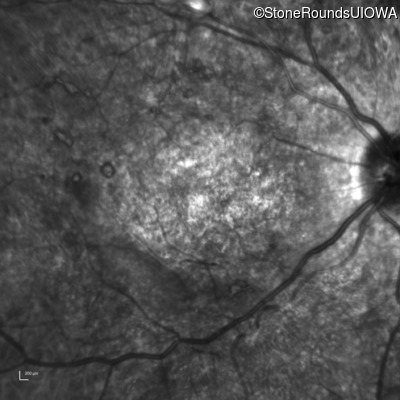

Infrared Fundus Photograph - Right - Count Fingers 3'

Exemplar